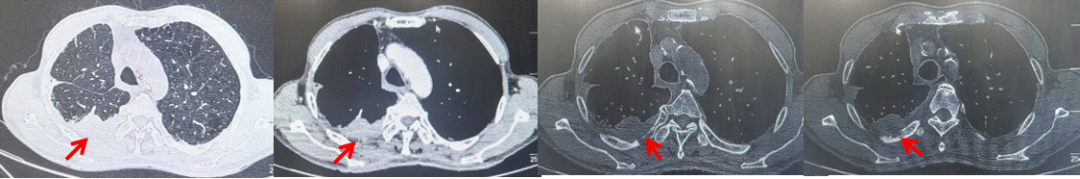

2024.11.19患者出现右侧胸痛,复查胸部CT检查示右侧胸膜肿物,大小约31mmX24mm,右侧4、5肋骨骨质破坏,考虑转移(如图2)。建议患者穿刺活检取病理明确诊断,患者拒绝,经MDT会诊后结合影像学表现及病史考虑为胸膜转移,肋骨转移,分期为rT0N0M1a IVA期,DFS仅仅17个月。2024.12.05起行信迪利单抗联合培美曲塞+卡铂方案治疗4周期,复查胸CT评效PR(如图3)。之后给予信迪利单抗+培美曲塞维持治疗6周期,期间复查CT评效PR(如图3)。目前信迪利单抗+培美曲塞维持治疗中,截止至目前PFS约为8个月,治疗期间未出现明显毒副反应。

图2:患者胸膜及肋骨转移(2024.11)胸部CT肺窗、纵隔窗及骨窗